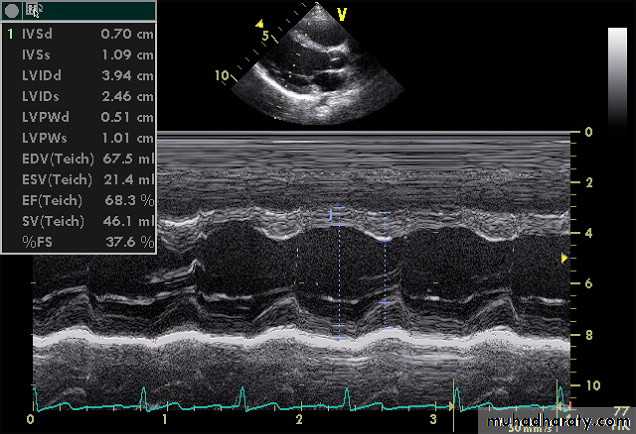

3-ECHOCARDIOGRAPHYEcho studies may confirm enlargement of ventricular chambers and impaired LV systolic function(low fractional shortening or ejection fraction) as well as impaired diastolic function by the use of Doppler techniques.